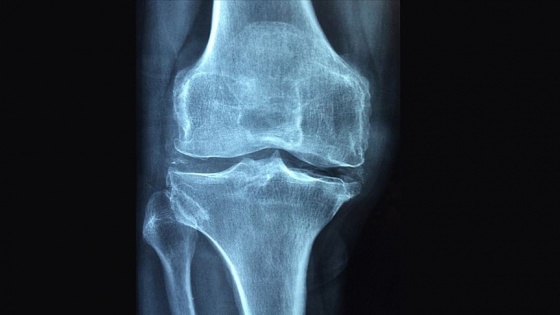

Kemik, kas ve eklemlerde iltihaba bağlı gelişen romatizmal hastalıkların, sık görülen kemik hastalıkları içinde yer alan ve halk dilinde kemik erimesi olarak bilinen osteoporoz riskini artırdığı belirtildi.

Romatizmal hastalıkların aynı zamanda osteoporoz gelişimi için de bir risk faktörü olduğunu vurgulayan Günendi, "Yapılan çalışmalarda iltihabi romatizmal hastalığı olanlarda, aynı yaş ve cinsiyetteki sağlıklı kişilere göre osteoporoz görülme sıklığının arttığı gösterilmiştir." dedi.

Osteoporoz ve osteoporoza bağlı kırıkların, romatizmal hastalığın kişiye ve topluma getirdiği yükün daha da artmasına neden olduğunu dile getiren Günendi, "Bu nedenlerle romatizmal hastalıklı kişilerde osteoporoz gelişiminin daha sık olabileceği unutulmamalı, diyet ve egzersiz gibi önleme girişimleri, uygun tarama yöntemleriyle erken tanı ve gerekiyorsa tedavi girişimleri yürütülmeli." ifadelerini kullandı.